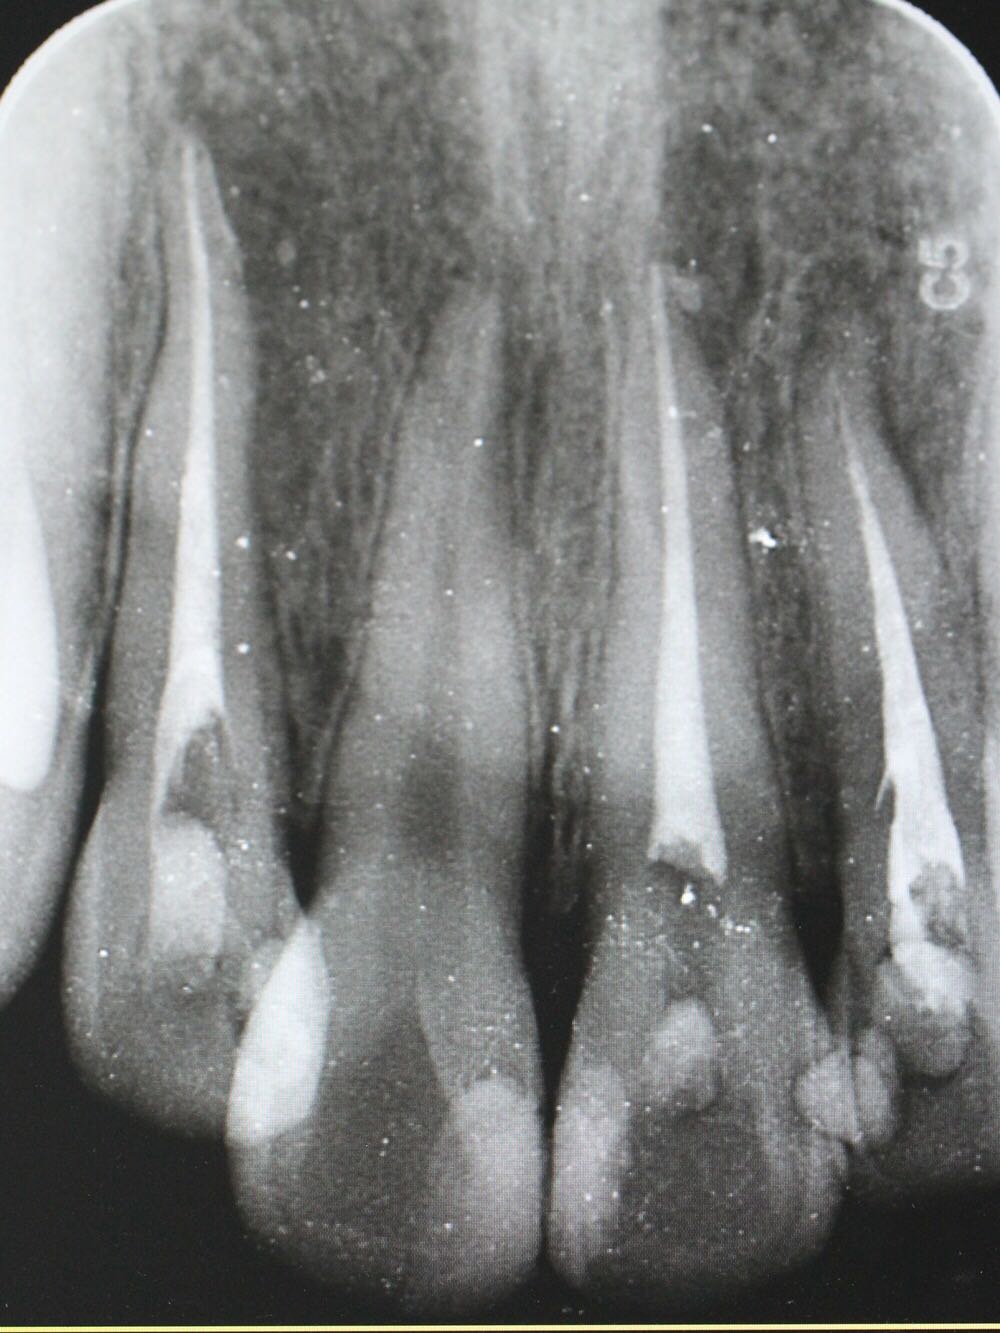

检查:12牙未见明显龋坏,探(-),冷(-),叩(++),无明显松动,牙髓电活力测试无反应,唇侧牙槽粘膜处未见窦道。 X线片:12牙根尖周暗影?

诊断:12牙牙髓坏死? 治疗方案: 1、12牙根管治疗+充填治疗+冠修复 2、12牙择期治疗 3、12牙显微根尖外科手术 4、12牙拔除 5、12牙观察 治疗计划:与患者交流沟通并详细介绍每种治疗方案、费用、时间、预后等,由于患牙根尖病变范围较大,预后欠佳。患者知情、同意并选择方案2,签署知情同意书。 12牙涡轮机开髓,探查根管口,10#,15#K锉疏通根管,根长测量仪测量根管长度,12牙22.5mm,髓腔和根管内放置根管润滑剂,S3扩锉至2506,拍片试尖,X线片示主尖合适。次氯酸啊冲洗根管,P5荡洗,纸尖干燥根管,置氢氧化钙,Caviton暂封。

处置:12牙去暂封,去棉球,根管及髓腔消毒并再次测量并确定根管长度,干燥后,显微镜下使用根尖孔生物材料加大锥度牙胶尖及热牙胶行根尖屏障封闭成形及根管充填,再拍X线片检查根充效果,X线片示根充良好,窝洞消毒,暂封。 医嘱:不适随诊,勿用患牙进食

侧切牙是畸形舌侧沟的好发牙位 釉质发生卷曲 一定程度后 可以形成牙中牙 该部位容易形成细菌通道造成根周的感染 治疗效果欠佳 在完善根管治疗后 应长期随访 必要时行外科手术 如果仍不能有效控制感染 则考虑拔牙